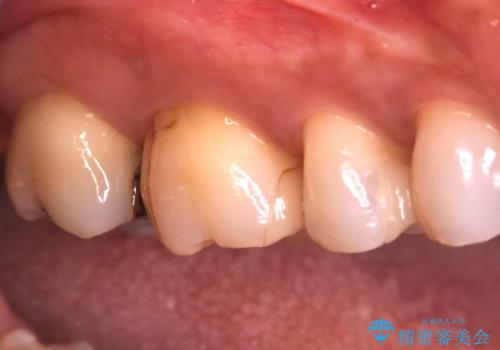

- 昔入れたメタルインレーの下にむし歯が再発したため治療を行った患者様です。

メタルインレーは汚れが付着しやすく、適合も悪いことがあるため、むし歯が再発しやすかったと思われます。

フロスなどの日常の清掃はもちろん不可欠ですが、メタルインレーより汚れが付着しずらいセラミックインレーにて今回は治療を行いました。